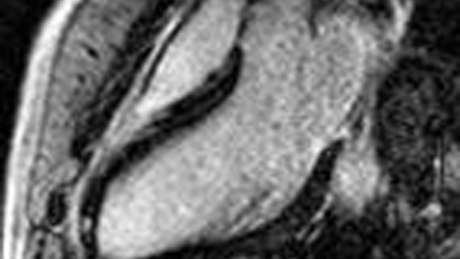

Bild 1-3: Darstellung einer Herzmuskelentzündung bei drei verschiedenen Patienten.

Der Herzmuskel ist jeweils dunkel, die entzündeten Areale kommen durch die Kontrastmittelanreicherung hell zur Darstellung.